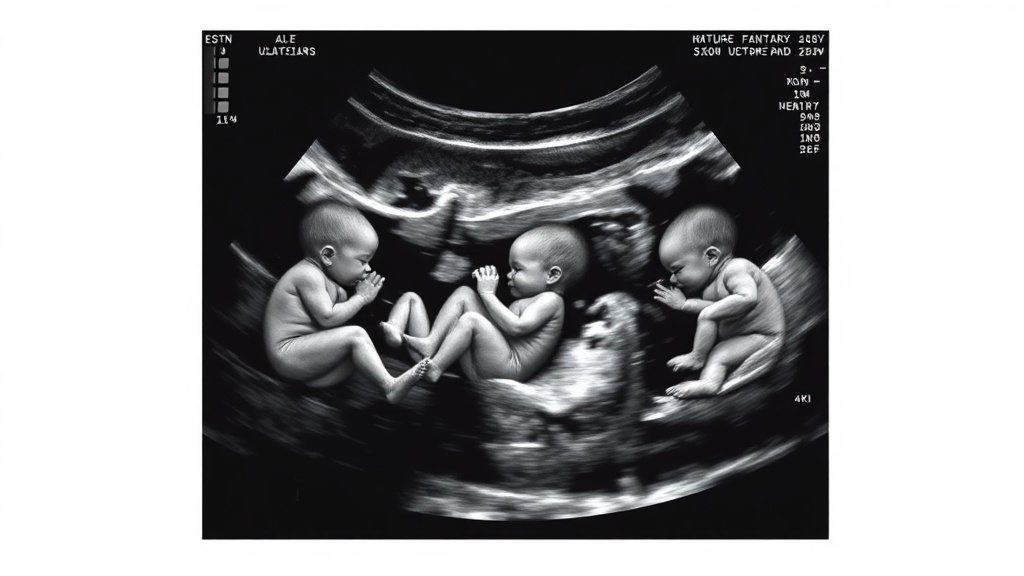

- Couple discovered they were expecting triplets during an ultrasound appointment.

A California couple's routine ultrasound appointment turned into an extraordinary revelation: they were expecting triplets. Stacie and Neal Radia, who had always dreamed of having at least three children, were astonished to learn they would soon welcome not one, but three babies. This natural conception of triplets is remarkably rare.

The couple's joy was compounded by the unique nature of the triplets: two identical twins, Alyx and Ella, and their fraternal sister, Charlie. The medical team monitored the pregnancy closely due to the potential risks associated with multiple placentas. Stacie reached 32 weeks gestation before the deliveries began.